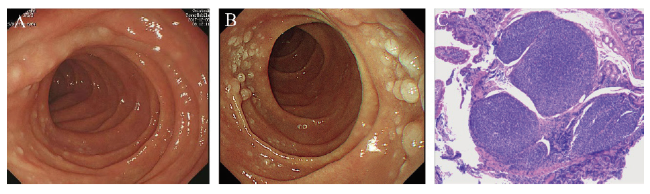

病例1 患者女,49岁,2019年6月20日于本院常规体检,主诉无明显不适,体格检查无殊。否认高血压、糖尿病等其他病史。血常规、血生化、肿瘤标志物等实验室检查均未见明显异常。腹部CT平扫示胃窦部胃壁稍增厚,肝囊肿,胰头部脂肪浸润。B超未见体表及腹腔深部淋巴结肿大。结肠镜示结肠黏膜未见异常。胃镜示十二指肠降段黏膜散在息肉样增生,表面粗糙,色灰白,病变分布于十二指肠乳头周围,占肠腔周径1/2~2/3(图1A);病灶黏膜病理:十二指肠乳头周围淋巴组织增生,黏膜内多个淋巴滤泡结构(图1B)。免疫组化:肿瘤细胞CD20(+),CD10(+),Bcl-2(+),Bcl-6(+),CD3(-),CD5(-),Ki-67(+,5%~10%),CD21 FDC(+)。结合HE染色及免疫表型诊断为D-FL(1级)。患者因无任何临床症状拒绝治疗,鉴于D-FL属于惰性淋巴瘤,预后较好,建议患者定期胃镜检查观察。2021年4月外院复查胃镜示十二指肠降部乳头处黏膜粗糙(图1C),该处组织病理为十二指肠降部黏膜慢性炎伴息肉状增生。确诊D-FL 4年,电话随访至截稿日患者主诉无不适感,虽未采取相关治疗,但疾病无进展迹象。

图1 病例1 D-FL患者胃镜及病理图片

注:A为2019年6月胃镜下十二指肠降段黏膜表现;B 为2021年4月胃镜下十二指肠降段黏膜表现;C为十二指肠降段黏膜病理结果(HE染色,40)。